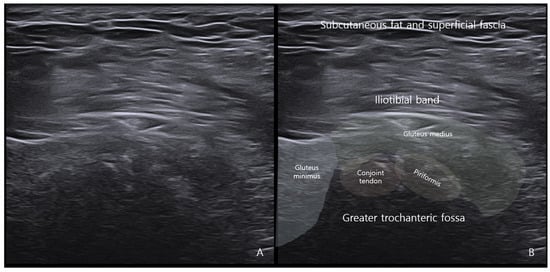

4.3.4. Ultrasound